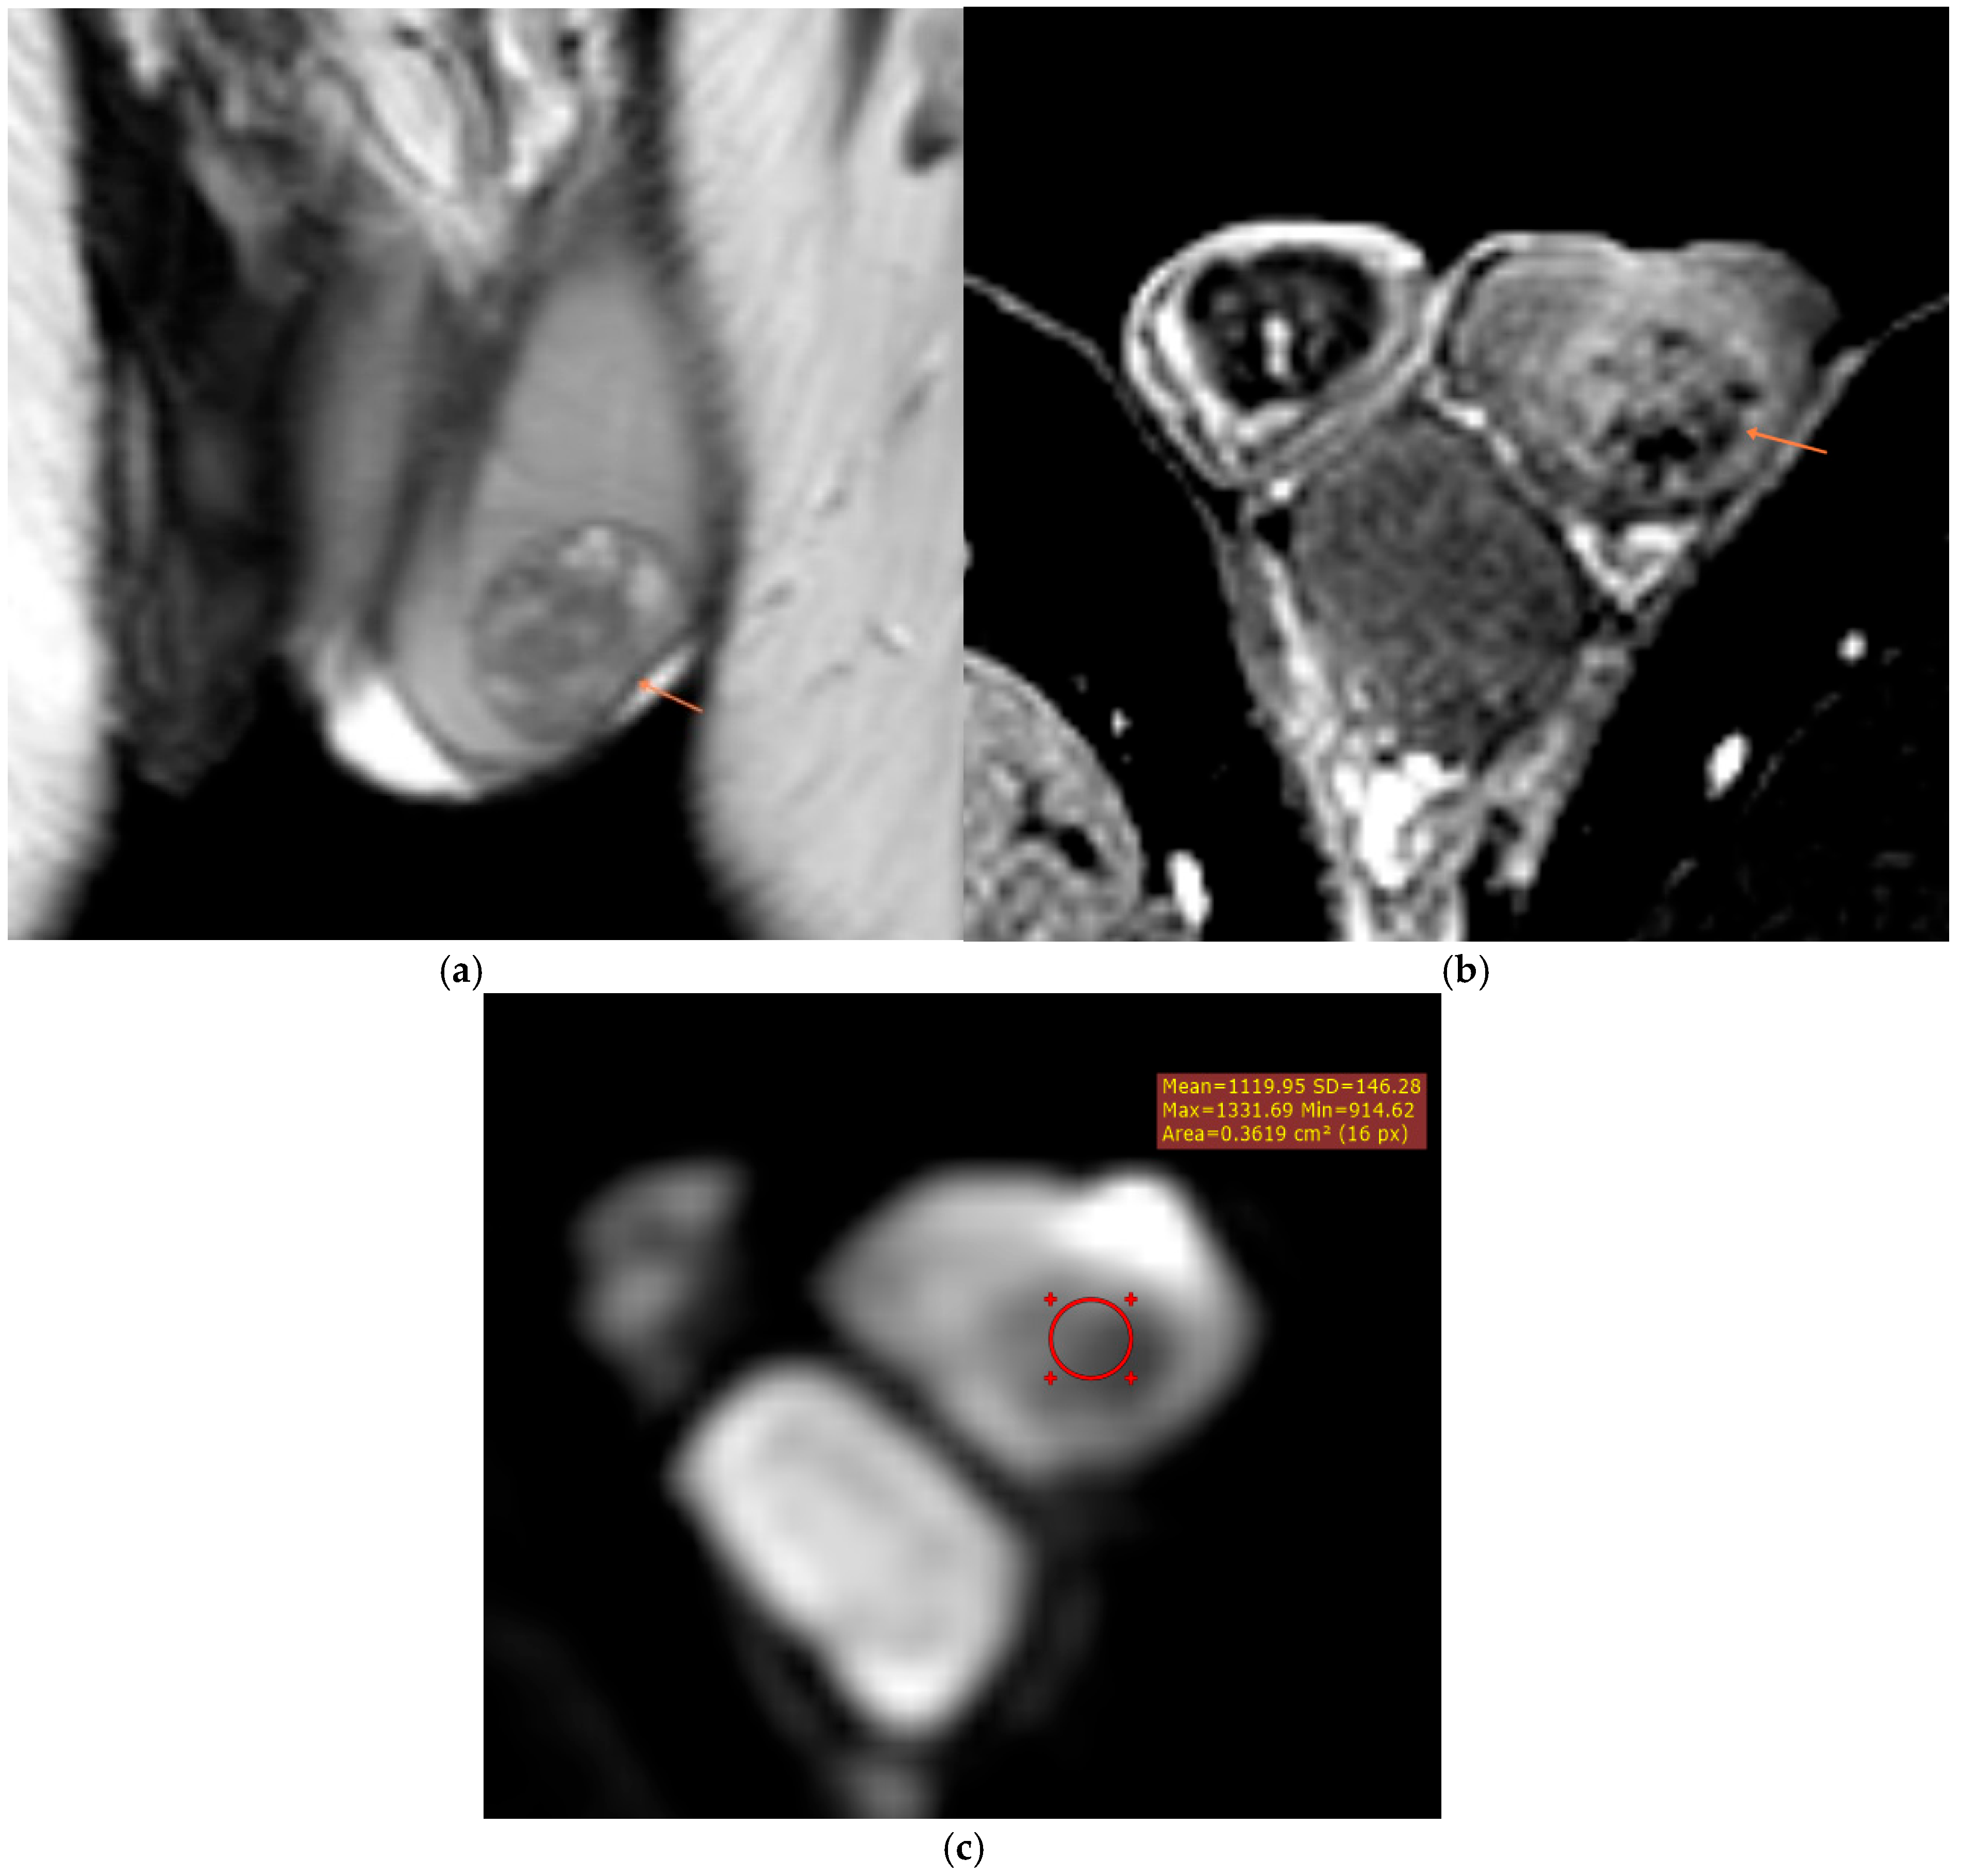

3.3.1. Intratesticular Masses

3.3.2. Paratesticular and Extratesticular Masses